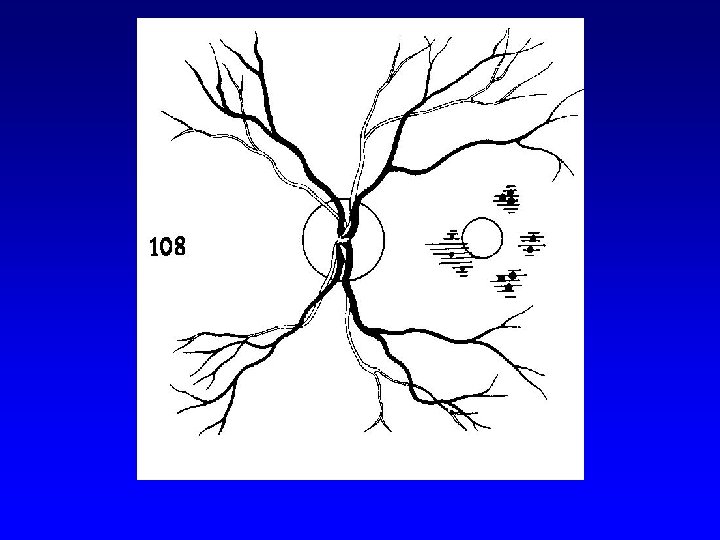

Laser therapy (technique) • Laser therapy of DR 1. focal 2. panretinal (scatter)

Laser therapy (technique) • Laser therapy of diabetic maculopathy 1. focal 2. grid

Focal laser